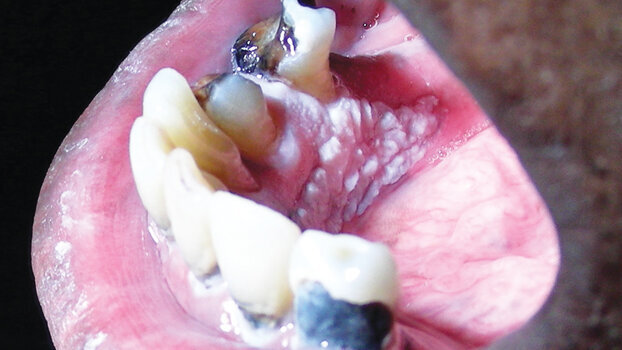

Malignancies of surface tissues, as seen in Figure 2, are often red and enlarged, and unexplained red lesions are often called erythroplakia.3 Unexplained red lesions are more likely than white lesions to be diagnosed as malignancies when they are biopsied because the expanding malignancy causes inflammation and secretes molecules that stimulate the formation of new blood vessels. However, both red and white lesions are capable of representing malignancy. Malignancies may also cause spontaneous pain or paraesthesia. The general rule of thumb is that unexplained red, white and/or ulcerated lesions that persist for more than ten days should be biopsied.

A lichenoid drug reaction, for example, is a reaction to a systemic medication that disappears when the medication is withdrawn. Lichenoid reactions also can result from contact with an allergenic material, such as a metal, in susceptible patients (Fig. 3), and for other reasons.